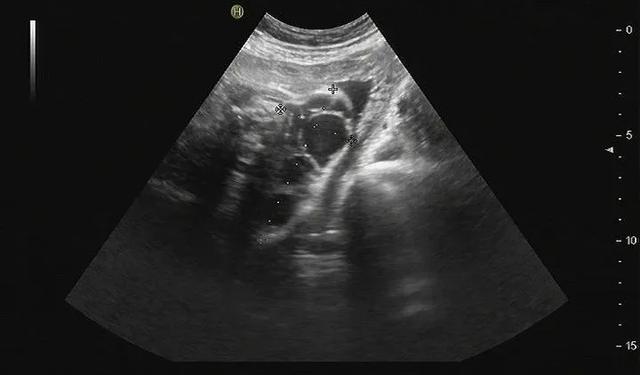

原来,王女士在当地产检时,当地医生发现在胎儿颈后有一个巨大囊性包块,大小约8cm,这几乎和胎儿的头等同大小。由于囊肿过大,且生长部位特殊,靠近胎儿的食管和气管,出生后极有可能产生压迫导致新生儿窒息等严重后果,当地医院建议到有着丰富“产前产后一体化”诊疗经验的青岛妇儿医院就诊,找寻解决的方法。

王女士怀着担忧的心情来到了妇儿医院胎儿医学门诊,接诊医生复查超声后确诊为巨大颈后淋巴管囊肿,并且已经对周围血管产生了压迫。根据胎儿的特殊病情,立刻组织胎儿医学会诊,我院小儿血管瘤专家、产科专家共同讨论,为王女士制定了包括出生后评估、随访、手术治疗的产前产后一体化诊疗计划。之后,王女士安心在我院接受相关产检,并于5月中旬顺利分娩。